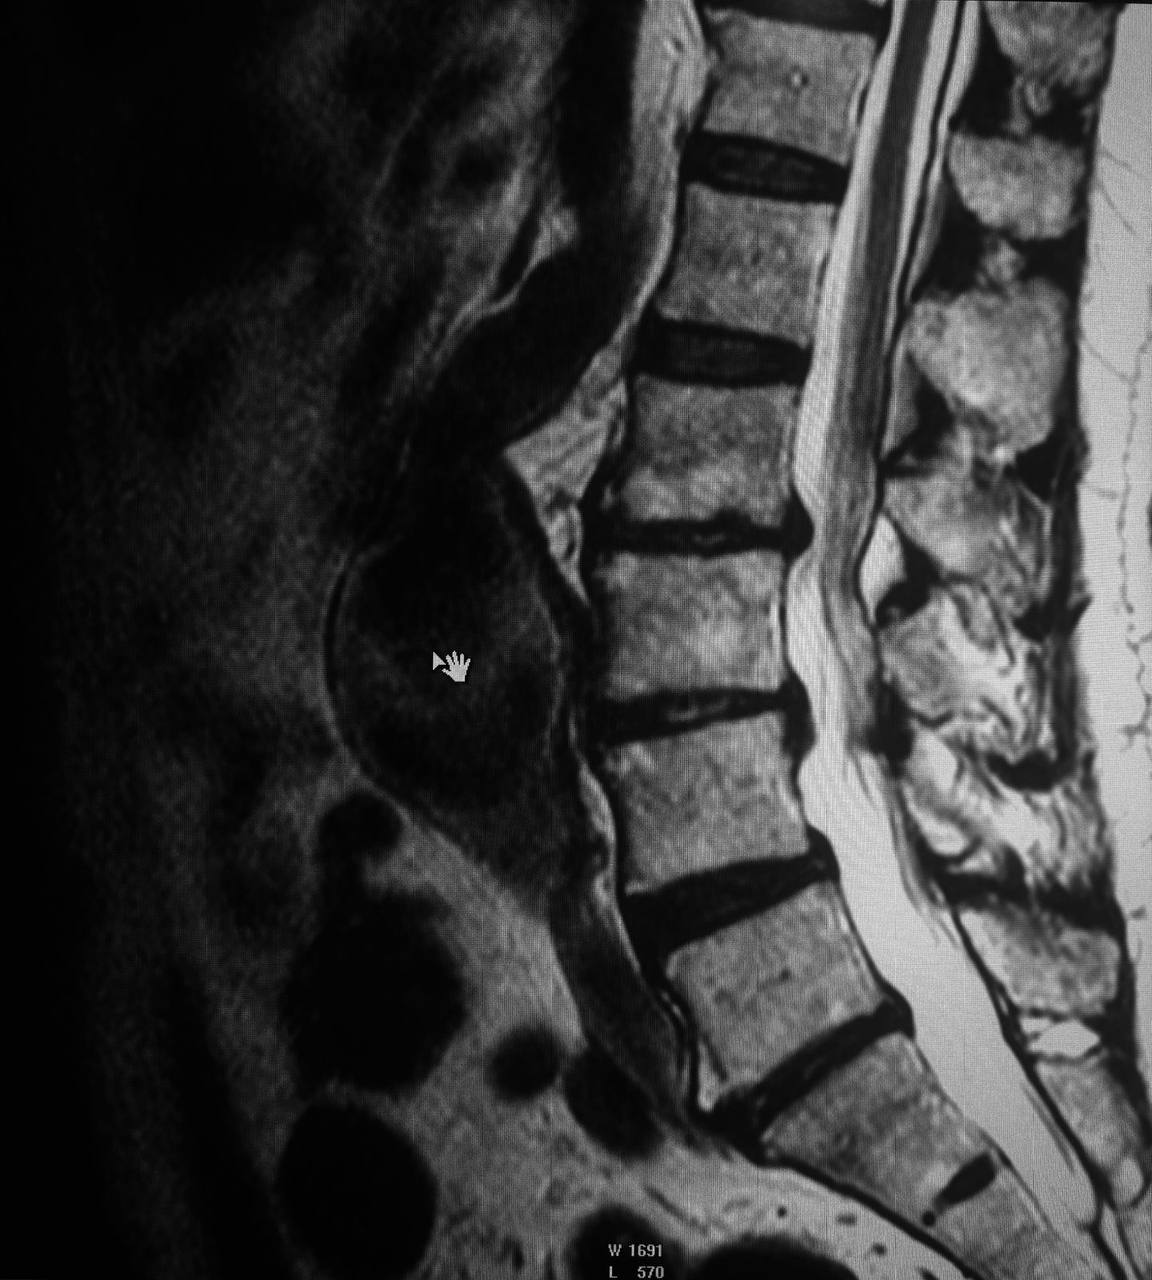

На прием обратился пациент (74 года) с жалобами на боли в спине. Для диагностики провели МРТ пояснично-крестцового отдела позвоночника, на котором и выявили крупную аневризму брюшного отдела аорты.

В анамнезе у пациента стентирование коронарных артерий и аортокоронарное шунтирование. Про аневризму брюшного отдела аорты он не знал, так как протекала бессимптомно.

Пациенту порекомендовали КТ с контрастированием для дообследования и консультацию сосудистого хирурга. Желаем здоровья и уверены, что такая «находка» поможет принять своевременные меры для его сохранения.